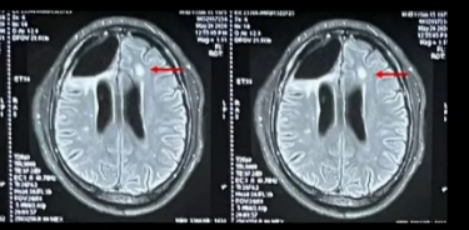

术后半年,2020年5年常规复查头MRI示左额皮层下白质新发片状Flair高信号(图4),临床表现稳定,继续随诊。

图4:左额皮层下白质新发片状Flair高信号